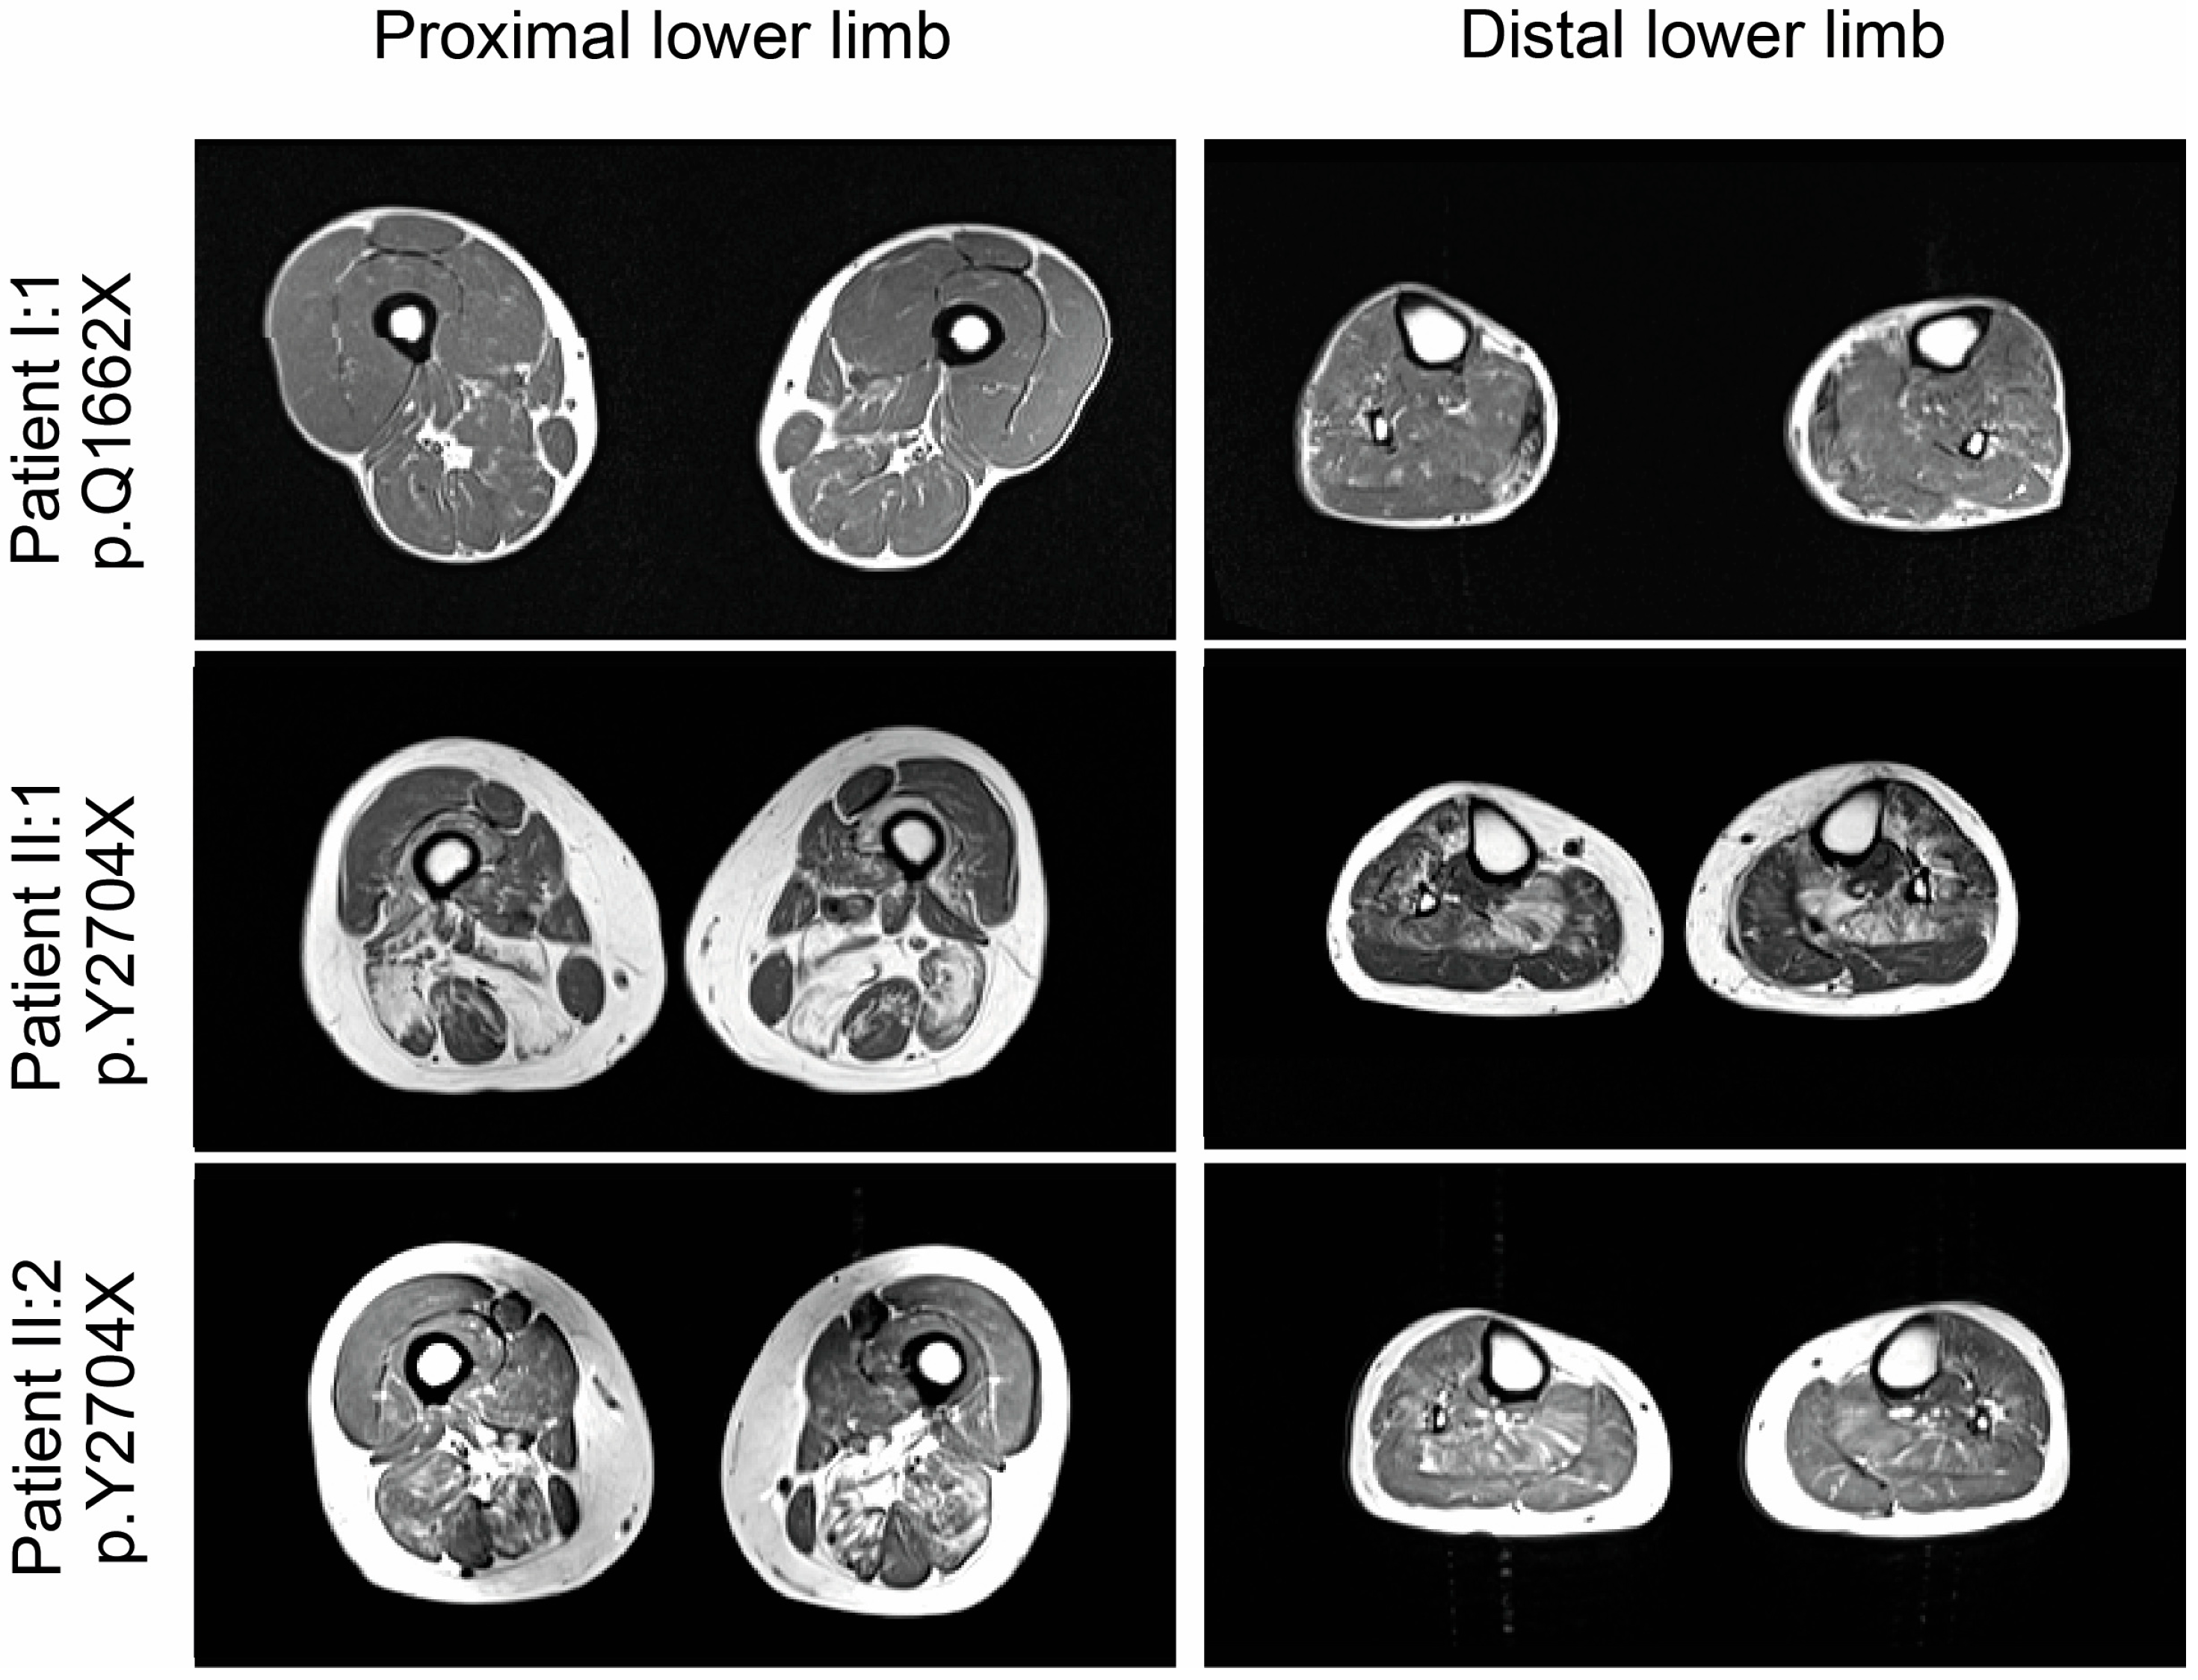

3.4. Magnetic Resonance Imaging (MRI) Studies

4.1. New FLNC Variants Lead to Selective Skeletal Muscle Involvement in p.Y2704X and an Overlap of Skeletal and Cardiac Alterations in p.Q1662X